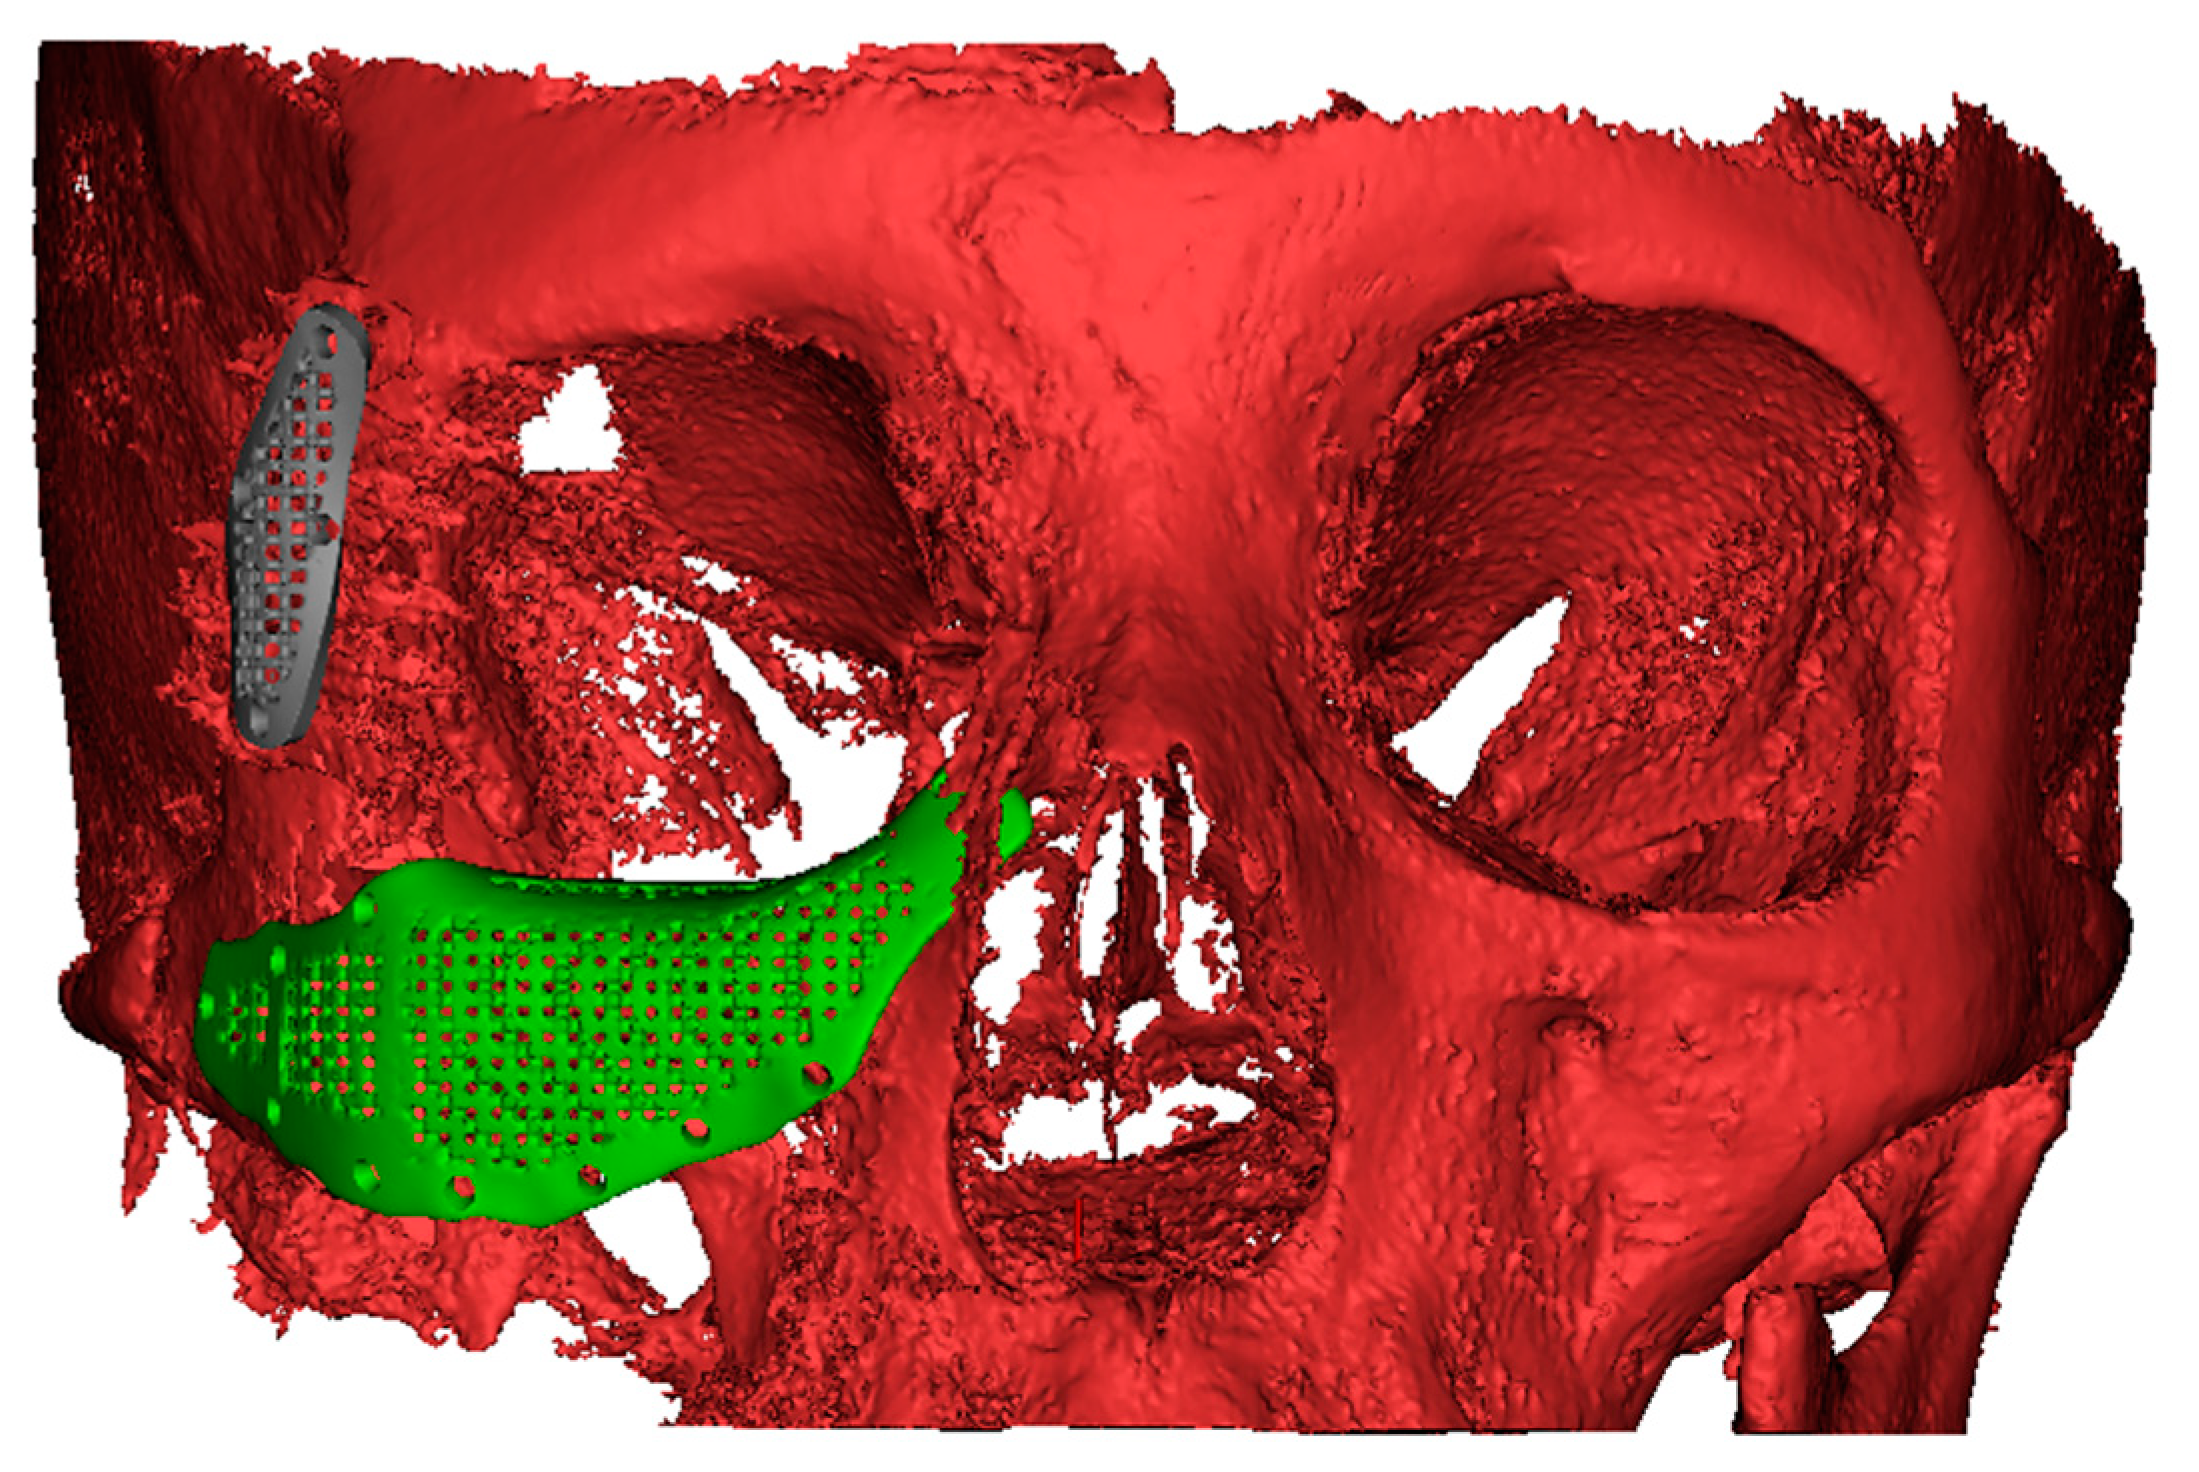

2.3. PSI Design

2.4. Virtual Planning of Patients-Specific Implants

2.5. Manufacturing of Patient-Specific Implants and Surgical Procedure